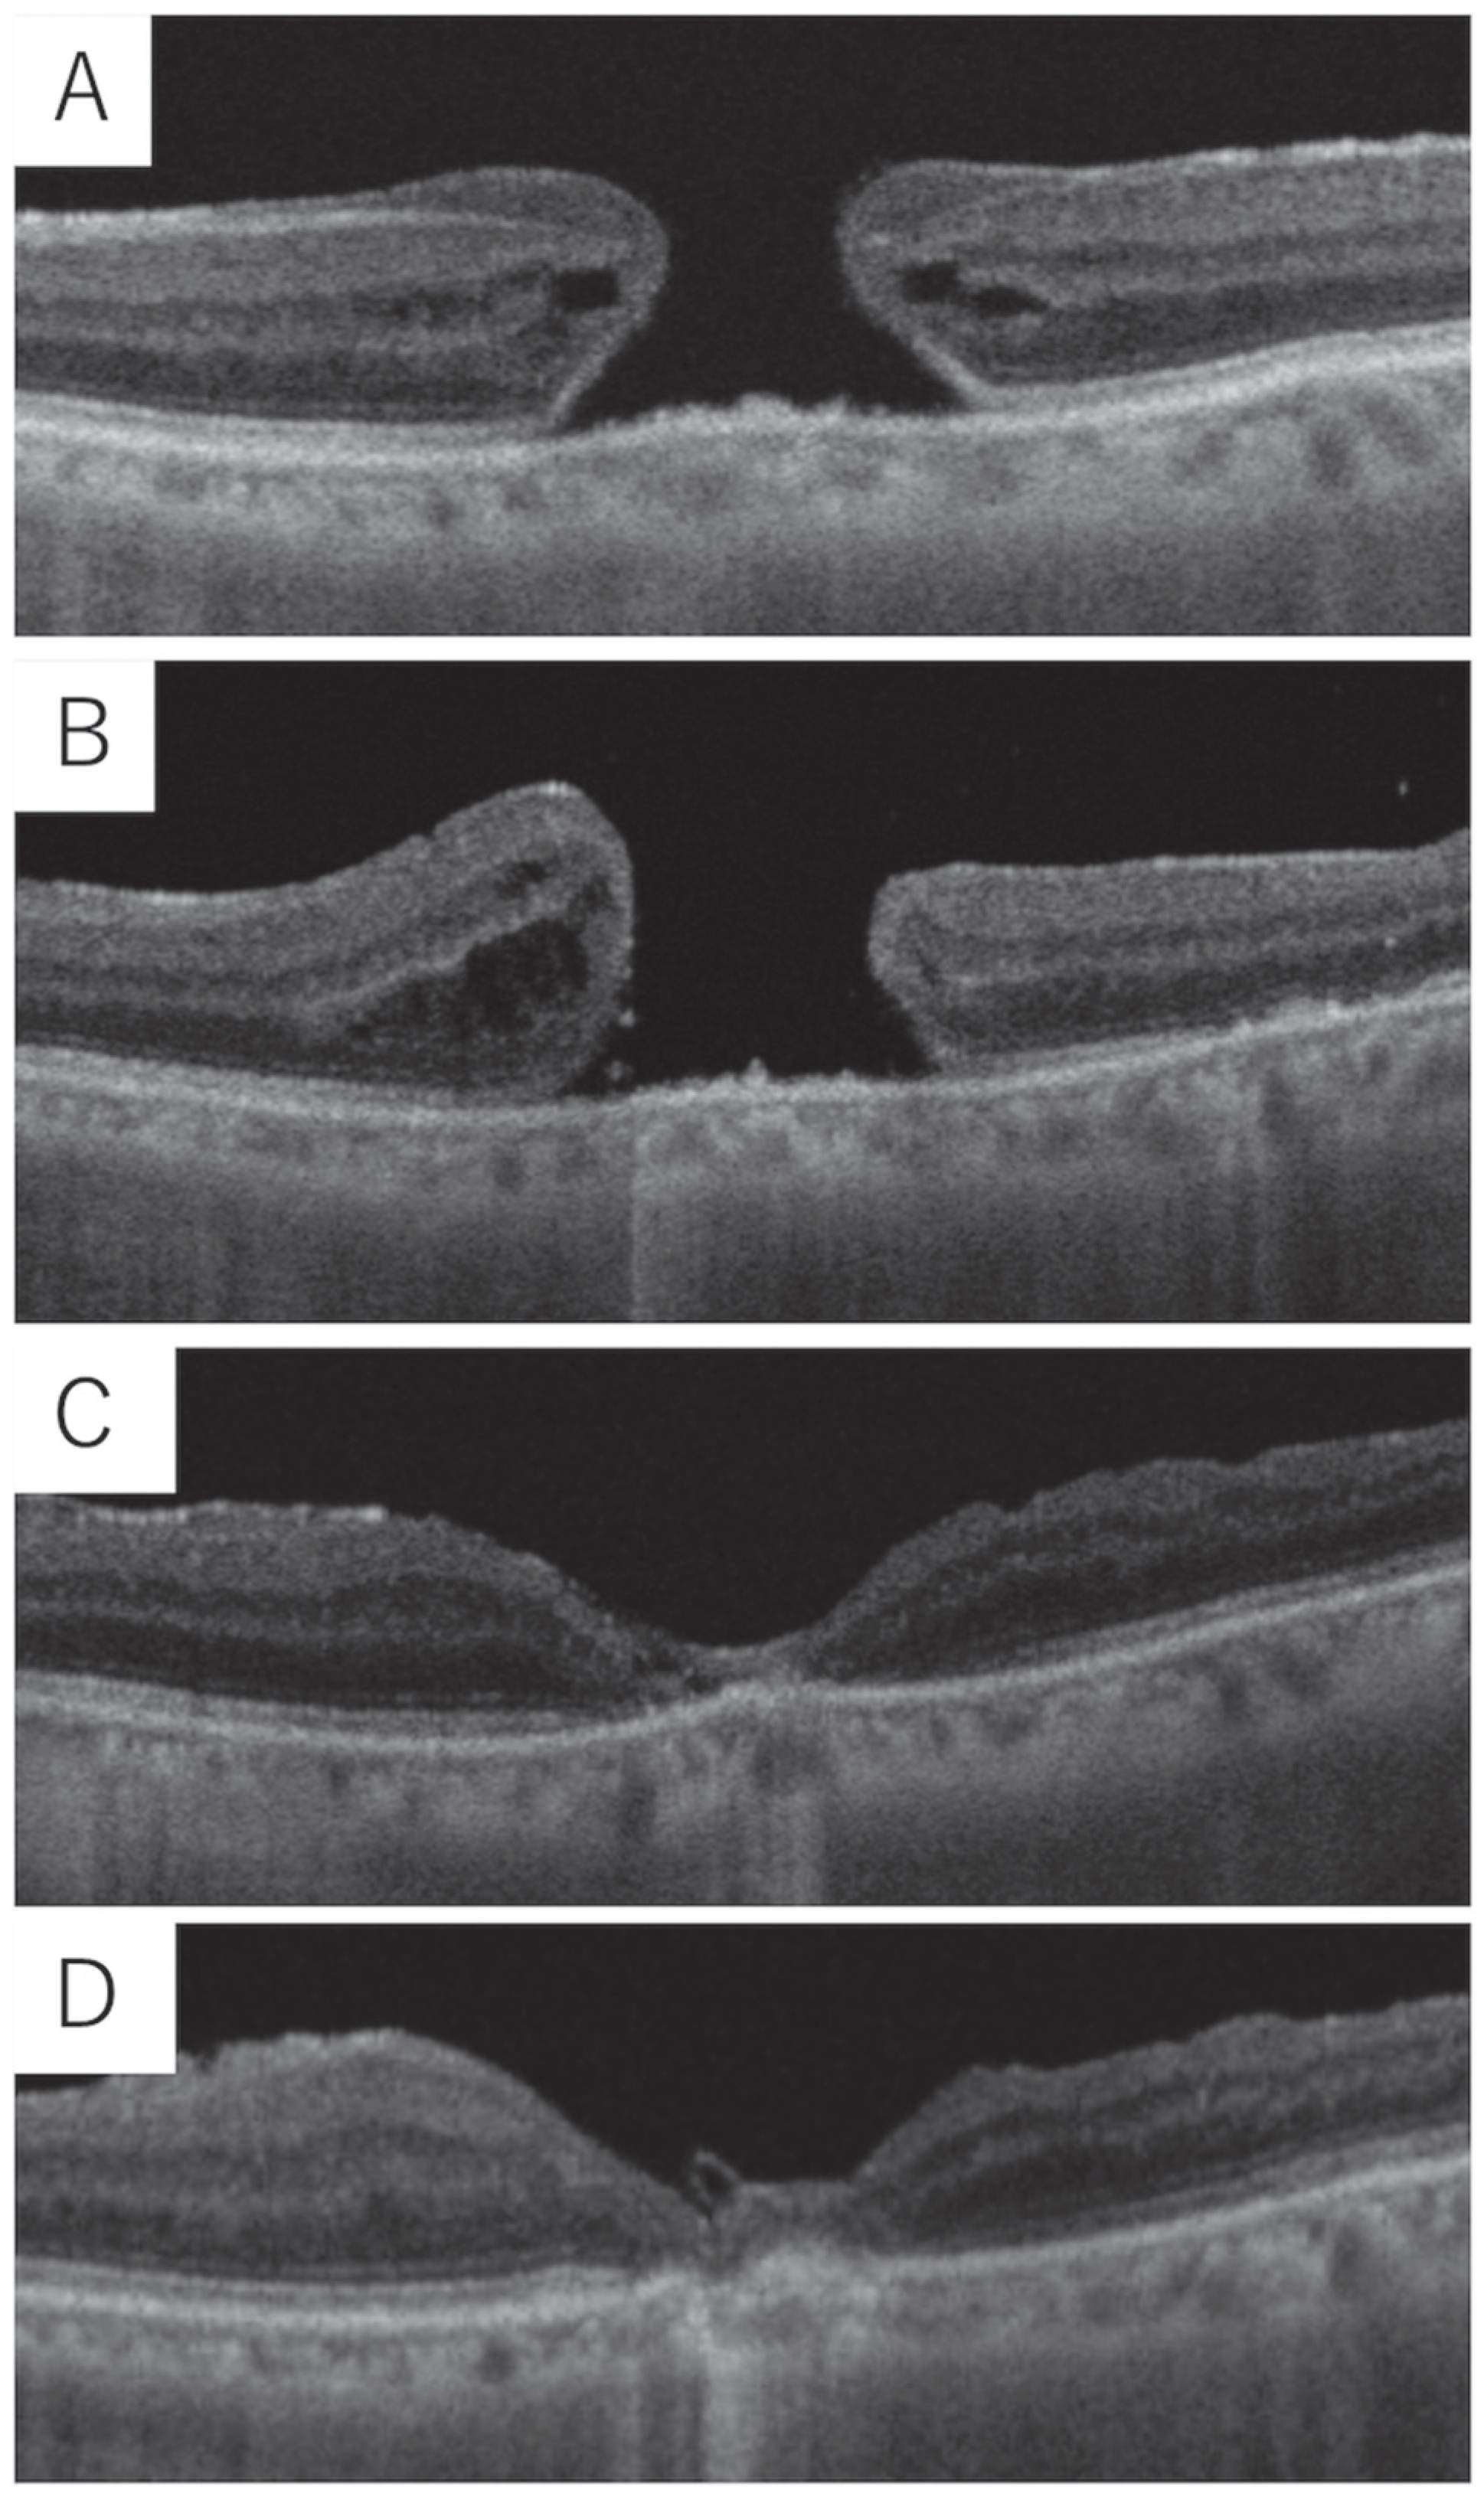

2.2. Clinical Characteristics and Clinical Course of FTMHs

2.3. Visual Acuity